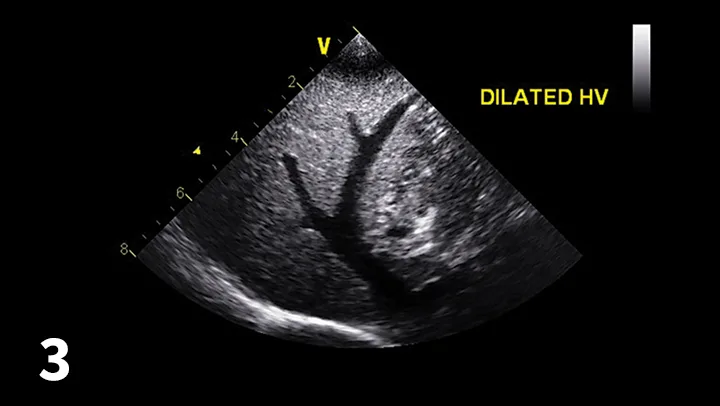

Abdominal ultrasonography is helpful to evaluate the patient for other underlying conditions and to evaluate the hepatic vessels (Figure 3).

Abdominal ultrasound image documenting enlarged hepatic vessels consistent with right-sided heart failure.